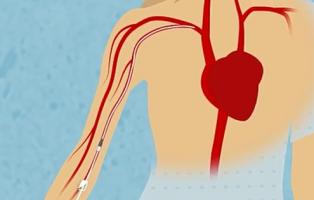

Actualité publiée le 04/06/2024STÉNOSE AORTIQUE : Remplacement valvulaire par cathéter ou chirurgie à cœur ouvert ?

PERSISTANCE du CANAL ARTÉRIEL: Le cathéter pour réparer sans chirurgie les bébés prématurés

Cathétérisme veineux, risque infectieux, et antiseptiques (1/4)

CATHÉTERS PICC : Un point sur les réactions allergiques

CATHETÉRISME : Pourquoi il faut réserver les PICC à une utilisation > 5 jours